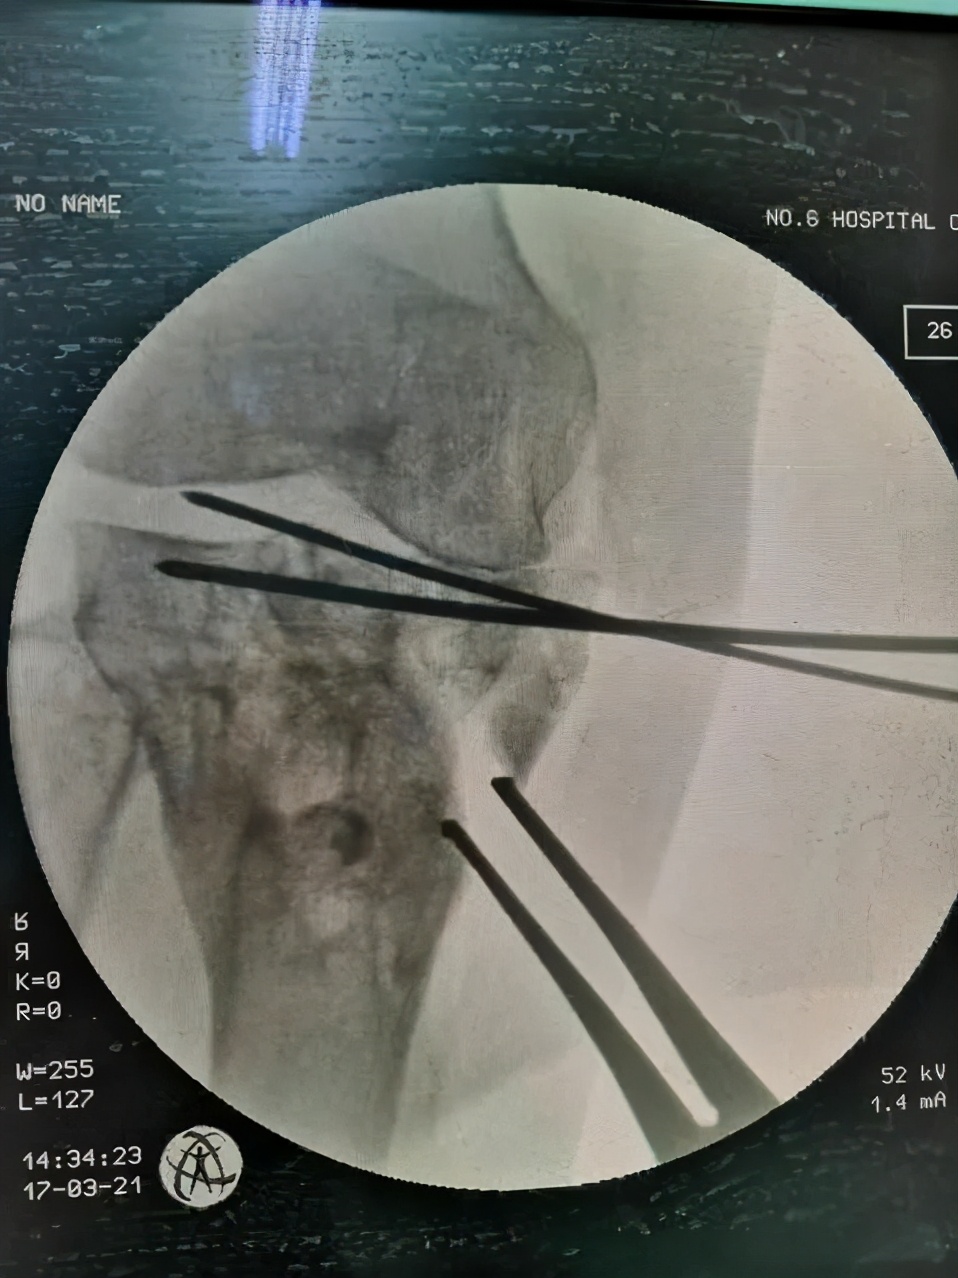

经过详细问诊以及X线检查,发现杨女士胫骨平台畸形愈合,平台大于股骨远端,膝关节对合不佳。刘万军主任决定行胫骨内侧髁截骨(TCVO),经过一系列周密的术前计划,刘主任为杨女士术前量身制作截骨模板,术后杨女士当天便可以下床活动,第二天就可以出院了,看见自己的腿由弯变直,杨女士的脸上露出了久违的笑容,对刘万军主任团队高超的医术赞不绝口。

术中

胫骨内侧髁截骨(TCVO)是一种胫骨高位截骨的方法,从胫骨内侧近端到胫骨髁间嵴(L型截骨),将内翻力线改变为外翻力线,治疗伴有膝关节向外侧半脱位的重度内侧间室骨关节炎的患者。